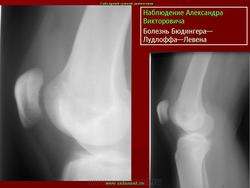

ХОНДРОПАТИЯ НАДКОЛЕННИКА (болезнь Левена). Этиология и патогенез. Чаще всего развивается после мелких повторных травм надколенника (у футболистов, бегунов, баскетболистов и т. д.), значительно реже — после однократной сильной травмы.